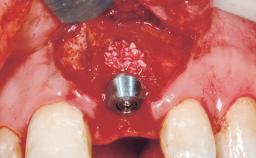

Late Placement of an Implant in a Maxillary Left Central Incisor Site

A 36-year-old female patient was referred for the replacement of the upper left central incisor (tooth 21), which had fractured. Although the tooth had been asymptomatic for many years, the crown began to loosen, at which time she presented to her dentist for an assessment. Teeth 21 and 22 had both been endodontically treated many years previously. She was a healthy individual and a non-smoker.

Bone Augmentation Horizontal|Staged

Augmentation Materials Xenogenous|Membrane

Bone Volume Deficient horizontally, requiring prior grafting